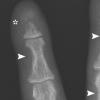

손가락뼈 갉아먹는 호르몬? 희귀 의학 사례